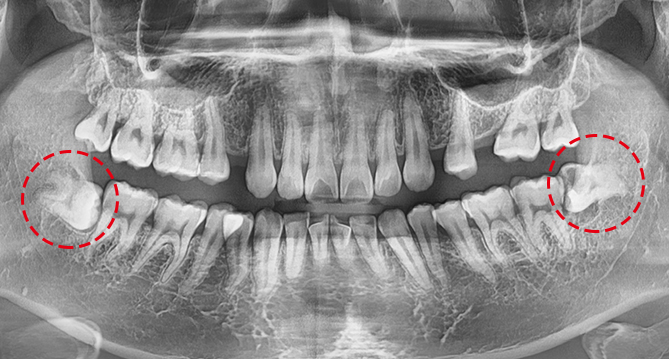

연세새빛치과 상악동거상임플란트 사례

연세새빛치과 전체치아교정[클리피씨] 교정 전